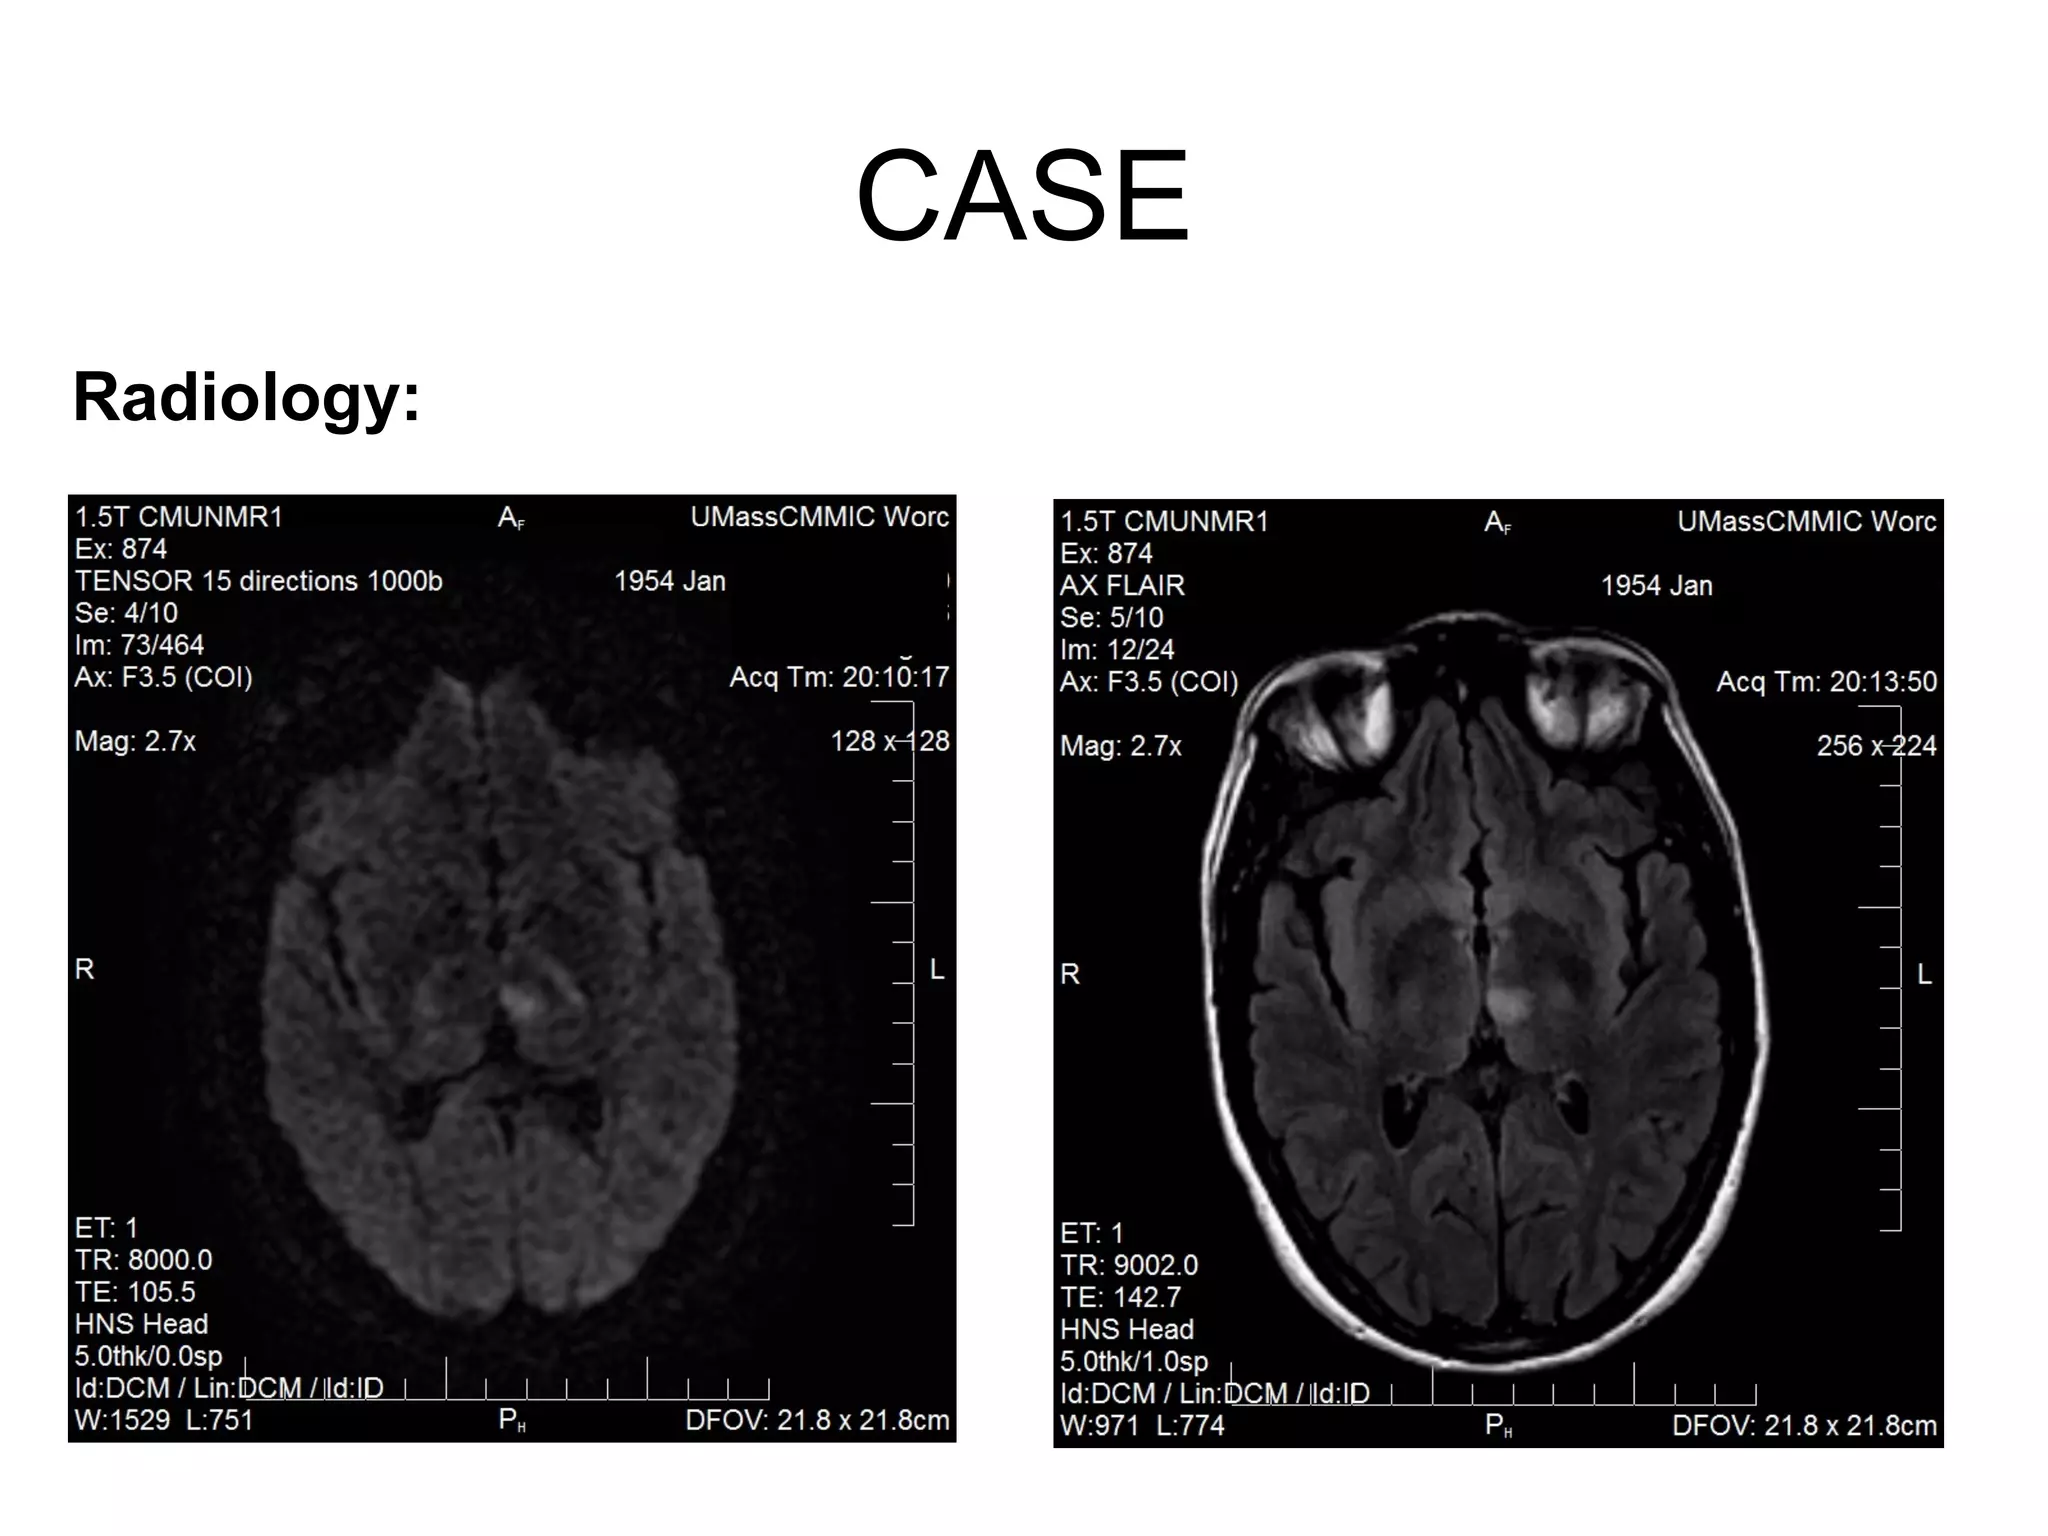

Radiology:

Radiology Cont:

MRI Brain – acute L thalamic infarction

CTA – No stenosis in the anterior or the posterior

circulation, small nodule L lobe of thyroid

TTE – evidence of ? ASD

CASE Radiology Cont: MRI Brain– acute L thalamic infarction CTA – No stenosis in the anterior or the posterior circulation, small nodule L lobe of thyroid TTE – evidence of ? ASD